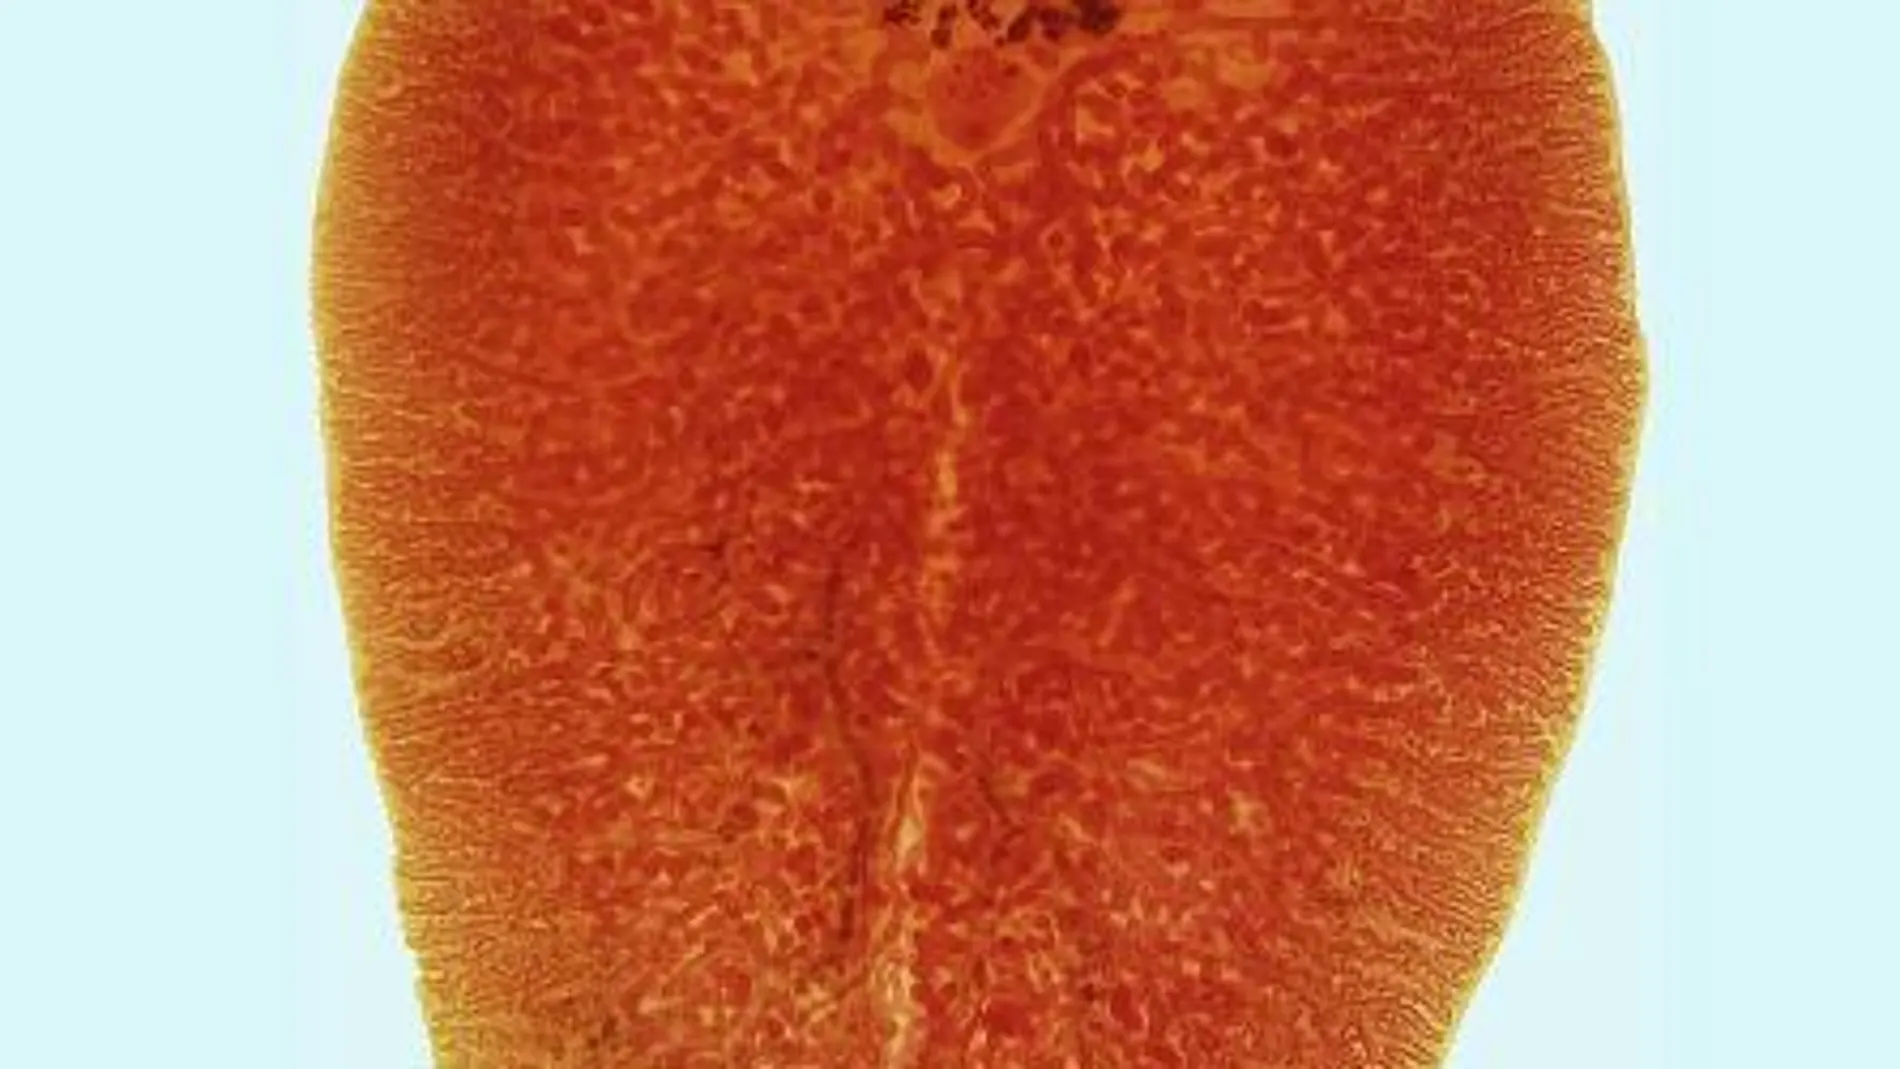

La Fascioliasis viene causada por un parásito del grupo de los helmintos que se desarrolla dentro del hígado y debilita su función. Éste se transmite a través de pequeños caracoles de agua dulce, cuya distribución mundial explica la problemática originada por esta enfermedad en todos los continentes, sobre todo en zonas rurales, aunque también en grandes ciudades.